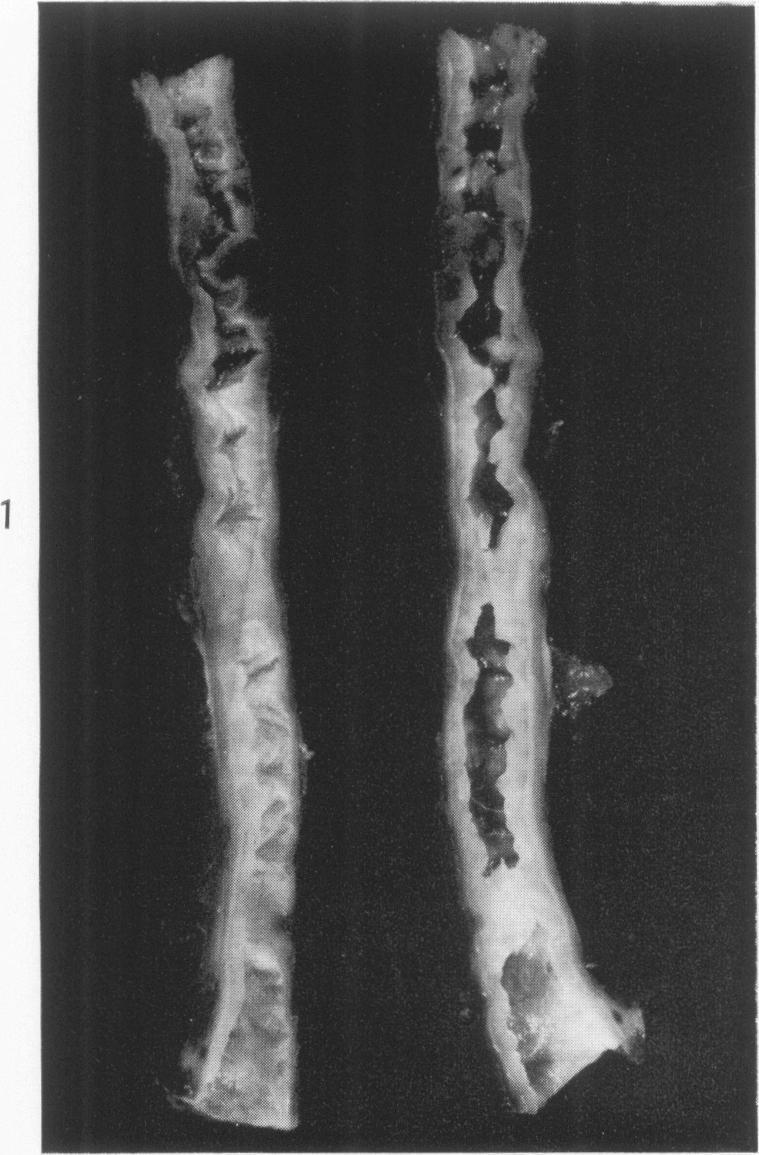

FIBROMUSCULAR HYPERPLASIA OF RENAL ARTERIES IN HYPERTENSION.

Am J Pathol. 1963 Dec;43(6):955-67.